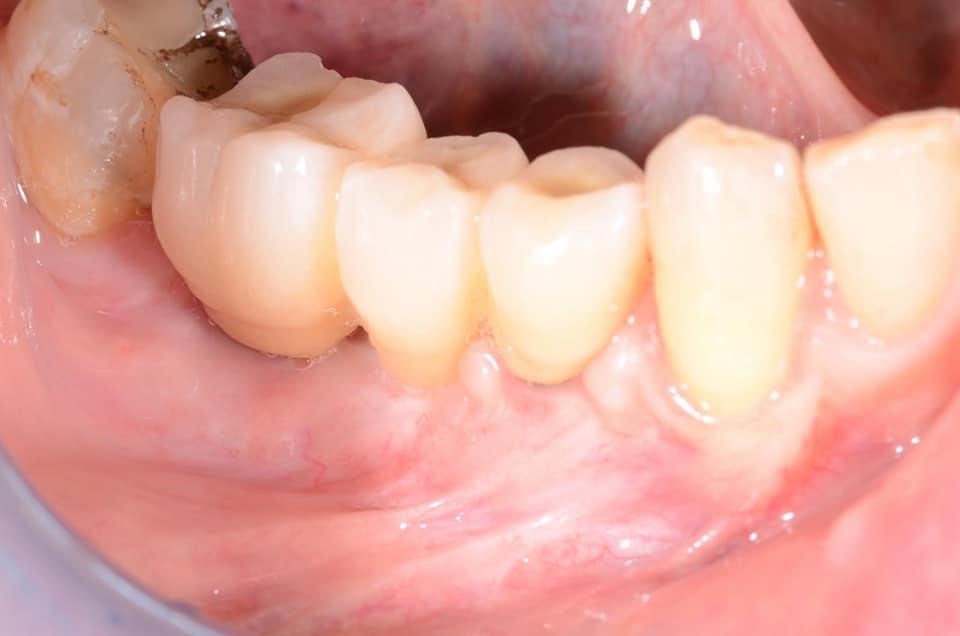

27/29 - Clinical view before installation of the fixed prosthetics, good amount of keratinized tissue around the implantsVertical bone augmentation and broadening of attached gingiva using cerabone®, permamem® and mucoderm® - Dr. R. Naimoli